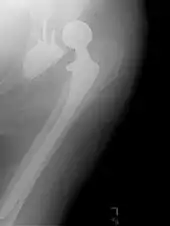

Hip replacement

An X-ray showing a left hip (right of image) that has been replaced, with the ball of this ball-and-socket joint replaced by a metal head that is set in the femur and the socket replaced by a cup